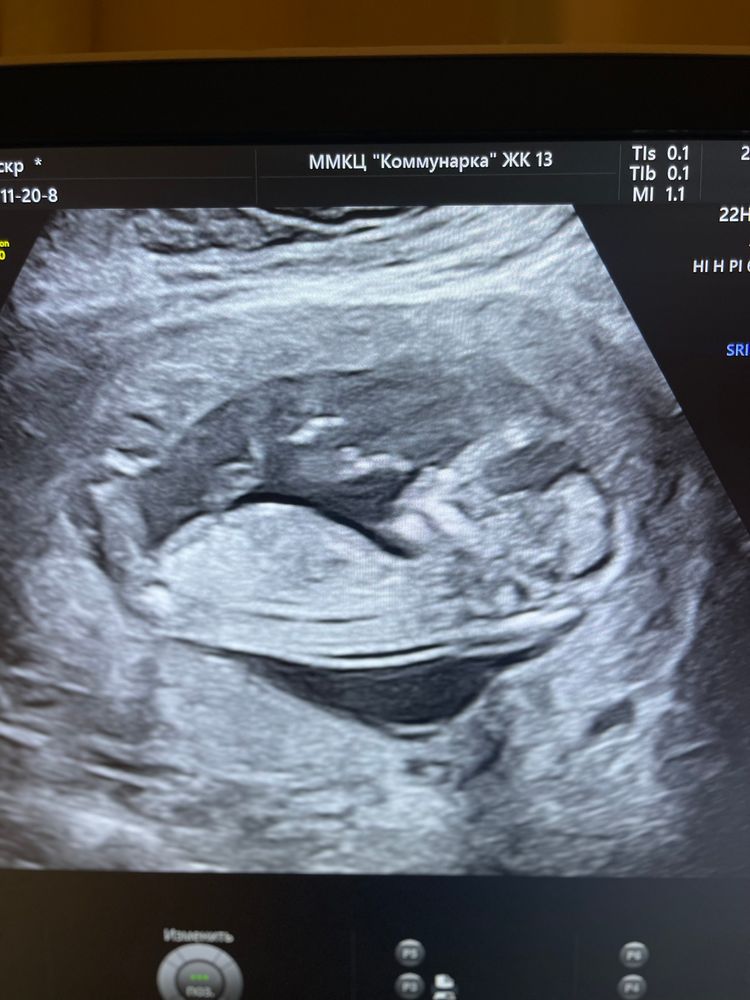

Подскажите , кто умеет определять пол малыша по половому бугорку, тут срок 12.5

По этому фото нет бугорка,нога.

За восходом, фото не удачное вышло)

Тут ничего не видно)

Алёна Хаустова, думала то что торчит и есть бугорок)

Эля, нет, это всё ножка и её составляющие)